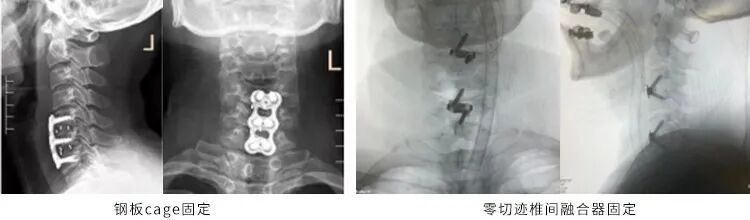

前路手术可分为钢板固定手术和零切迹椎间融合器固定。

尽管内固定系统前方钛板的支撑能够维持颈椎的稳定性,提高椎间融合率, 矫正颈椎生理曲度,但在双节段以及多节段颈椎病当中,其弊端也十分明显,如螺钉松动、软组织剥离过多、压迫食管以及术后异物感等。为了减少以上颈椎并发症的发生,目前新型的颈椎前路零切迹椎间融合器的应用越来越多。

大量研究显示: 越短越薄的钛板能够减少颈椎前路手术异物感的发生率。大多数学者认为是外植入物钛板刺激前方的食管导致颈椎术后异物感。零切迹内固定系统将内固定完全植入椎间隙与上下椎体中,避免了前方钛板的植入与软组织肌肉过多剥离,因此能减少术后异物感的发生率。所以我们现在颈椎前路手术小于三个阶段的一般都可以用零切迹融合器手术治疗。

同时,零切迹融合器能够避免前方钛板的植入,减少颈椎前方软组织的剥离,从而减少了术后颈部异物感的发生。手术时间短,术中出血少,操作相对简单,组织剥离少,并发症发生率低,有望替代传统钛板联合融合器内固定系统。